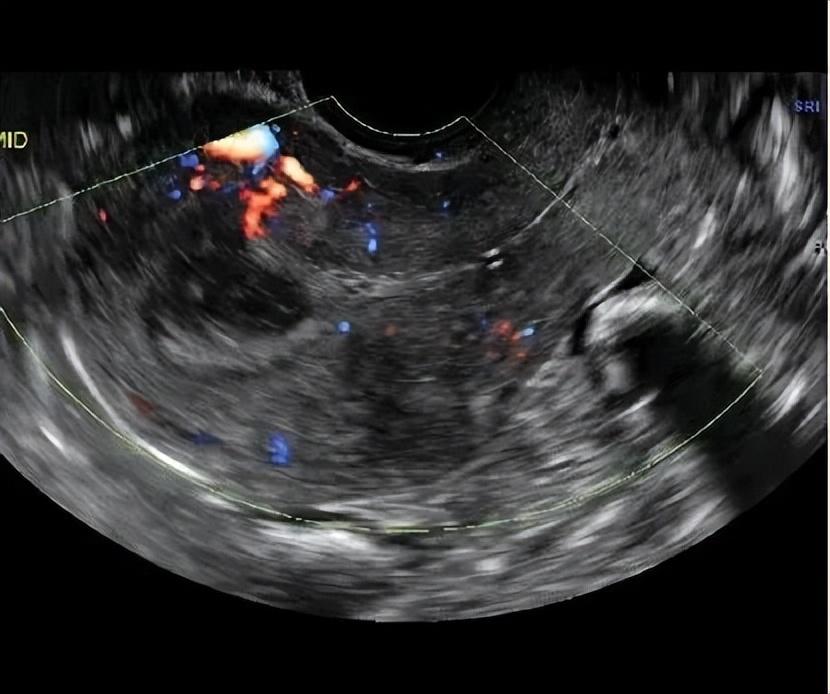

流产后复查超声,结果报告显示血流信号不丰富,不像典型的子宫动静脉畸形,这与之前的CT血管造影和临床病史产生了矛盾。

当宫腔压力降低时,它看得不清楚,这也解释了为什么怀孕时能发现,清宫后反而超声显示血流信号不丰富的原因了。

经阴道彩超是首选筛查工具,医生可以看到子宫里有一个富含血流信号的团块,多普勒技术能测到里面血流速度极快、阻力极低的特征,但本案例清宫手术后超声典型特征消失,可造成误诊。